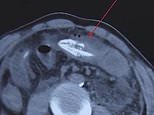

A Chinese man nearly died after allegedly inserting a wiggling 16-inch eel into his backside to treat his constipation. The picture shows an X-ray scan of the patient in southern China

Dr Li from the hospital told the local media: ‘[We] suspected that there was a foreign object in his abdominal cavity from a CT scan. But we couldn’t tell where it came from.’